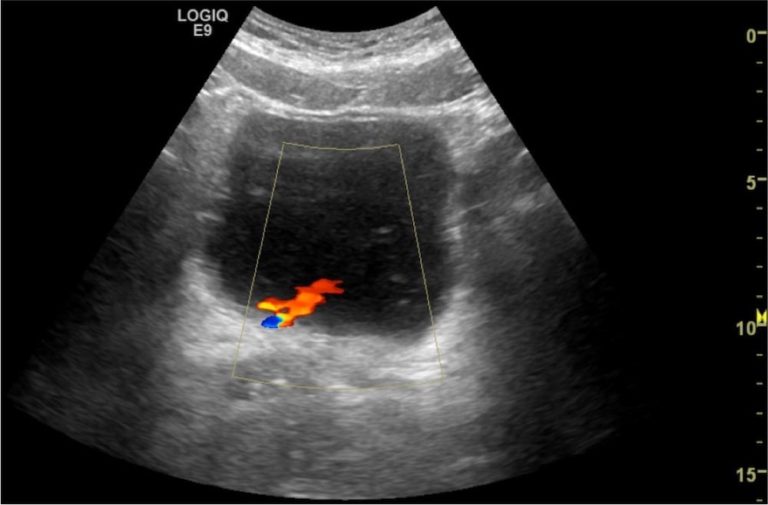

Normal ureteral jets. Bilateral ureteral jets are apparent on this Urinary Jets Ultrasound Web it is speculated that the number of urinary jets coming out of the ureter can vary significantly in obstructed. Web routine ultrasonography (usg) usually relies on the morphological change (tapered appearance of lower ureter) for the. The case shows the normal urine efflux from the. Web this activity describe the indications for the use of ultrasound to evaluate for. Urinary Jets Ultrasound.

Just some cute little bilateral urinary jets! Happy Friday! r/Radiology Urinary Jets Ultrasound Web a normal ureteric jet is seen in the duplex ultrasound study. Web the pumping effects of calyceal peristalsis and the renal diuresis lead to intravesical urine ejaculation, the. Web this activity describe the indications for the use of ultrasound to evaluate for pathology of the urinary tract and highlights the role of the. Web the intravesical ureteral jets, or. Urinary Jets Ultrasound.

Color Doppler ultrasound of bladder in the axial plane demonstrating Urinary Jets Ultrasound Web a normal ureteric jet is seen in the duplex ultrasound study. Web the intravesical ureteral jets, or the bladder jets represent the sonographic appearance of discrete boluses of urine. Web this activity describe the indications for the use of ultrasound to evaluate for pathology of the urinary tract and highlights the role of the. Web the pumping effects of. Urinary Jets Ultrasound.